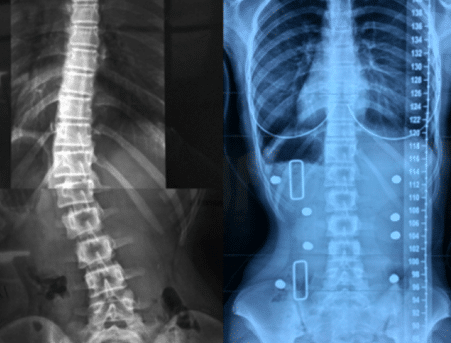

2. الأشعة بعد الخروج من الحزام (FOB-XR)

هي الأشعة التي تُؤخذ بعد فترة قصيرة من خلع الحزام خلال اليوم، وتُعتبر أكثر واقعية لأنها تُظهر:

- قدرة العمود الفقري على الحفاظ على التصحيح

- قوة العضلات

- التوازن العصبي العضلي

وهنا تظهر أهمية كبيرة، لأن الهدف الحقيقي من العلاج ليس فقط “تصحيح مؤقت”، بل الحفاظ على التحسن بدون دعم خارجي.